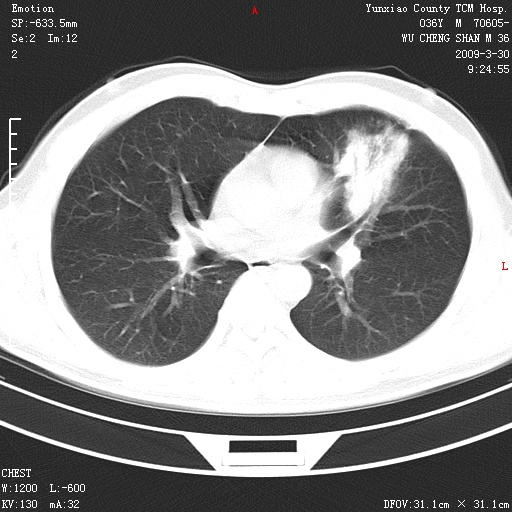

本院家属,胸痛,无咳嗽咳痰发烧病史,治疗一个月后病灶无明显改变,支气管镜示左肺慢性炎症,未见癌细胞,

胸痛,无咳嗽咳痰发烧病史,治疗一个月后病灶无明显改变,支气管镜示左肺慢性炎症,未见癌细胞,左肺下叶前段片状影,边缘不清,内见空支气管征,纵隔未见淋巴结肿大,周围无卫星灶,应考虑为炎性病变。

胸痛,无咳嗽咳痰发烧病史,治疗一个月后病灶无明显改变,支气管镜示左肺慢性炎症,未见癌细胞,左肺舌叶片状影,边缘不清,内见空支气管征,周围无卫星灶,应考虑为炎性病变。

左肺舌叶片状影,边缘不清,内见空支气管征,炎性病变